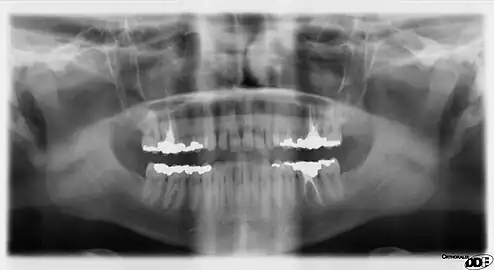

![]() An orthopantomograph, which uses focal plane tomography. | |

In radiography, focal plane tomography[1] is tomography (imaging a single plane, or slice, of an object) by simultaneously moving the X-ray generator and X-ray detector so as to keep a consistent exposure of only the plane of interest during image acquisition. This was the main method of obtaining tomographs in medical imaging until the late-1970s. It has since been largely replaced by more advanced imaging techniques such as CT and MRI. It remains in use today in a few specialized applications, such as for acquiring orthopantomographs of the jaw in dental radiography.

Panoramic radiography is the only common tomographic examination still in use. This makes use of a complex movement to allow the radiographic examination of the mandible, as if it were a flat bone.[11] It is commonly performed in dental practices and is often referred to as a "Panorex", though this is a trademark of a specific company and not a generic term.